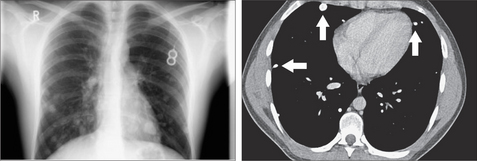

image

Figure 21.4 Multiple small nodules. Some are much smaller than 10 mm but are readily visible. This suggests that they are calcified. Indeed, they do contain calcification as shown on the CT section (arrows). Secondary tumours from a primary osteogenic sarcoma.